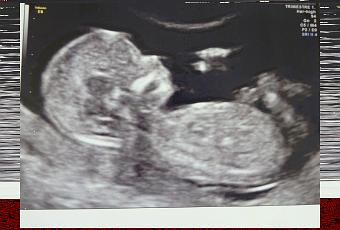

NOME: Paciocco

ALTEZZA: 7,6 cm

RESIDENTE in: Pancia di MI

SEGNI PARTICOLARI: orecchie a punta!

Vi presento ufficialmente la nostra meraviglia! La dottoressa stamattina ci ha fatto un super servizio fotografico da tutte le angolazioni. La ginecolga mi ha detto di andare in bagno a fare pipi' (e meno male perchè non riuscivo più a trattenermi!) e al ritorno...voilà, il piccolino si era girato e ci mostrava il suo profilo migliore! La dottoressa ha detto che è proprio un bimbo ubbidiente e gentile. :) Speriamo lo sia anche dopo la nascita. Abbiamo visto quindi tutto il necessario, comprese le cavità del cuore, gli emisferi cerebrali, i cristallini nell'occhio in via di formazione, la spina dorsale, lo stomaco, la minuscola vescichina (ehi questo mi fa pipi' in pancia!), le dita delle mani e dei piedi (cinque per fortuna in ogni mano) e le orecchie... a punta! Sembrava il Dr Spock di Star Trek! Ma niente di strano, la dottoressa ci ha detto che è normale che le orecchie siano cosi' perchè si stanno ancora formando.

Secondo tutte le misurazioni fatte, lo sviluppo è normalissimo e la crescita coincide perfettamente con la data presunta di concepimento. Per quanto riguarda i parametri di riferimento per lo screening della trisomia 21, non c'è alcun motivo per sospettare rischi di questo tipo. Il valore della translucenza nucale è di 1,14 mm ed è ben al di sotto del valore soglia (3 mm). Anche le ossa del nasino sono presenti, il che di solito non avviene appunto nei bambini Down.